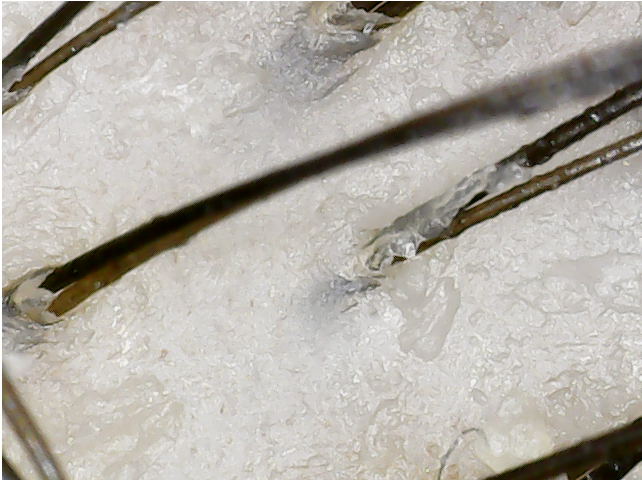

since i was 19 i was loosing my hair with a white bulb at the end of it. About a year and a half ago I went to the dermatologist about my hair loss. She checks my hair with a otoscope for about 10 seconds and does a pull test and tells me i have alopecia and dandruff. Then i tell her that hairs that fall have this white bulb at the end of it and its been going on since i was 19 tells me that i have telogen effluvium. then i get prescribed finasteride, ketoconazole 2% shampoo, and minoxidil 7%. Now 23 still use finasteride, ketoconazole 2% shampoo but not minoxidil 7% it irritated my scalp did use minoxidil 5% but stop after 5 months saw no improvements. About 3 month still loosing lots of hairs but do see less falling and its been going like that since then but recently i started loosing lots of hair again. I'm pretty sure I have chronic telogen effluvium (my scalp is very visible when wet and oily) but I also think I'm loosing my hair because of sebum. My hair gets oily through out the day and after I sleep and wake up I'm just covered in oil I do shower every morning. After I shower I let my hair dry and I comb it and there's just tons of hairs falling out nothing new but now its lots more. I'm posting pictures of my scalp and the white bulb if anybody has any ideas what's going on on my scalp.